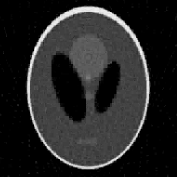

We use the Shepp-Logan phantom, available, for instance, in the Matlab Image Processing toolbox (see Figure 1). The phantom is sized , with . The projection data (i.e., sinogram) of the simulated phantom is corrupted by a white Gaussian process with zero mean and variance.

The reconstructions of the Shepp-Logan phantom are shown in Figure 4. Plots of the sparsity levels, as the iteration progresses, are reported in Figure 6. For the 120 projections case, the proposed approach converges in 885 iterations, while, in the 30 projections case, it converges in 301 iterations. As figure of merit, we use the relative error: the obtained values are summarized in Table 2, where we also report the values of the relative error obtained for the FBP reconstructions.